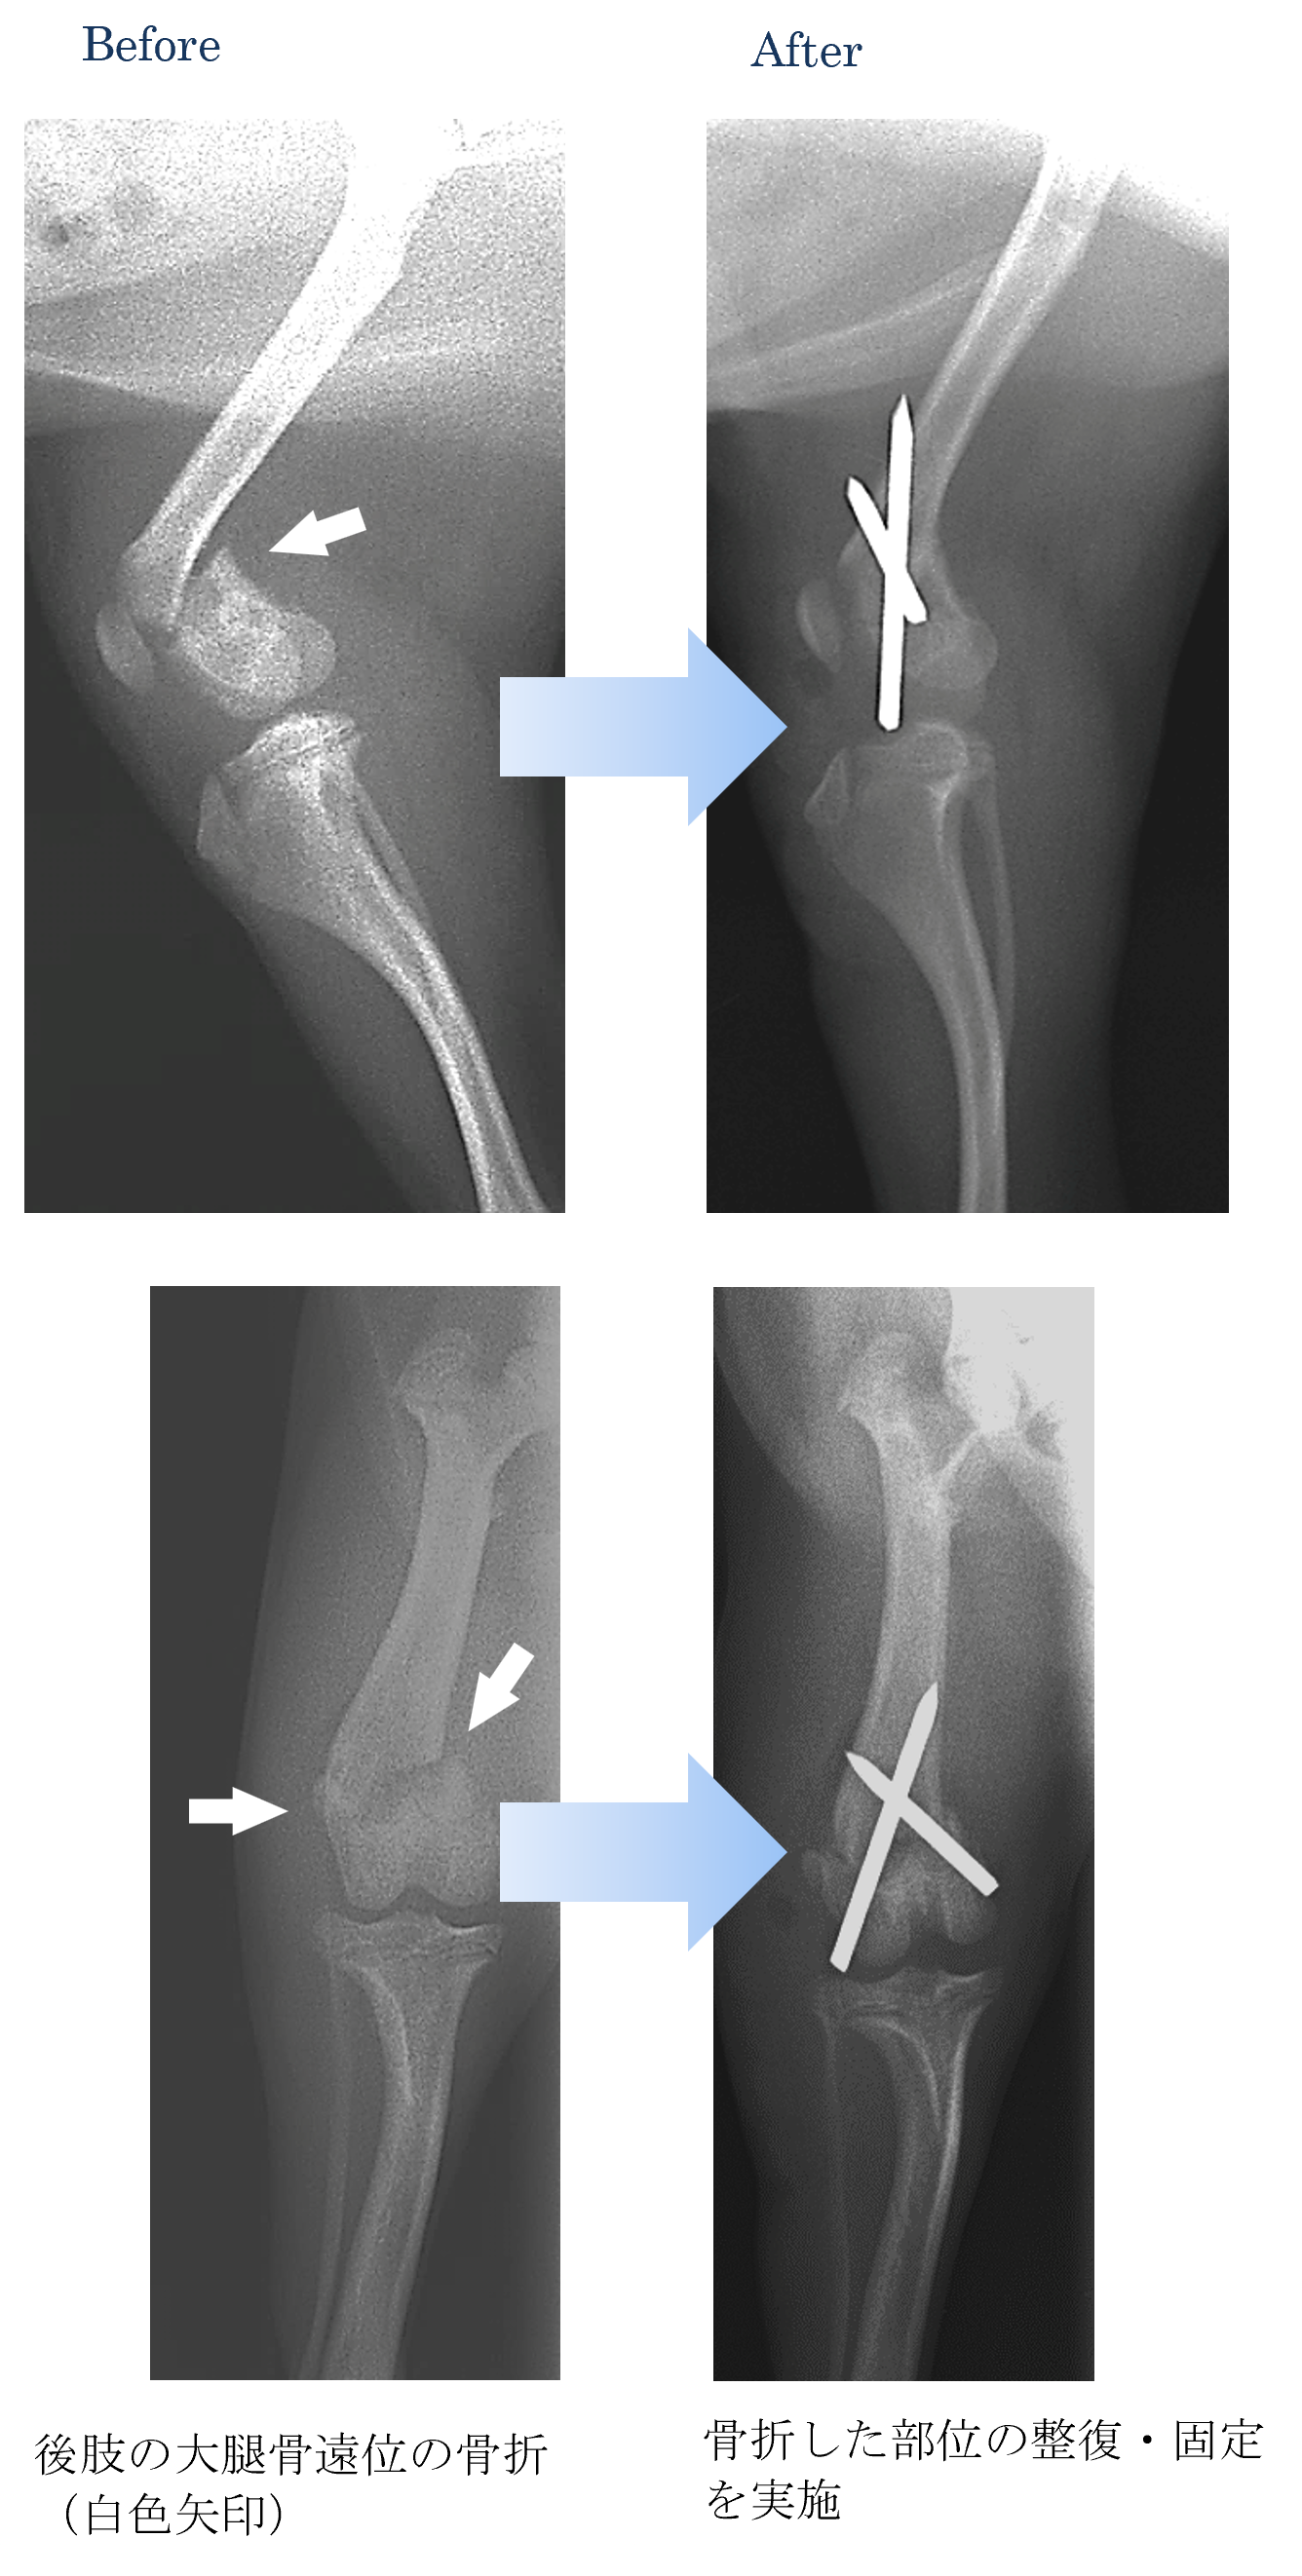

各種検査より、大腿骨(太ももの骨)の遠位(足先)骨折と診断しました。

ご家族と相談した結果、手術による骨折の整復および固定をすることになりました。

術後も順調ですぐに走り回り、以前の元気になりました。